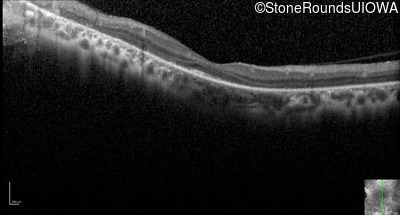

Optical Coherence Tomography - Left - 20/50 +1

Exemplar / OCT Stack